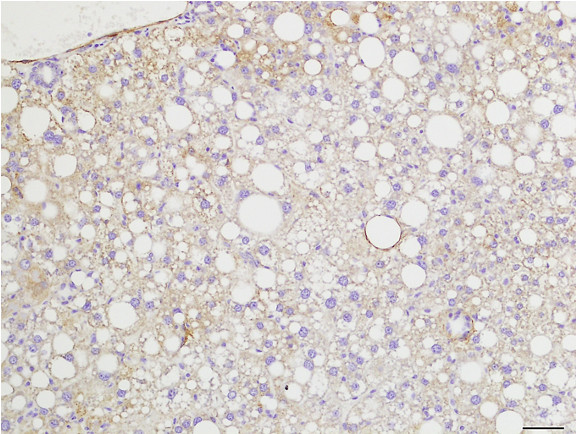

Figure 6: Histopathology for C57BL/6NTac mice placed on D09100310 diet (MASH B6NTac) or kept on chow diet (Control B6NTac) from 6 weeks of age. Animals were on diet for 27, 35 or 53 weeks. Hematoxylin and eosin (H&E) staining illustrates morphological changes including steatosis and infiltration of immune cells. Activated HSCs were identified in liver sections by using a rabbit polyclonal antibody to alpha-smooth muscle actin (a-SMA) (1:500 dilution; ab5694; Abcam, Cambridge, MA) which was detected by an anti-rabbit IgG embedded polymer with embedded horseradish peroxidase and visualized with 3,3′-diaminobenzidine (DAB) chromogen (Agilent, Carpentaria, CA). Hepatocellular lipid droplets were identified by visualization of the lipid-binding protein adipophilin known to be expressed in steatotic livers. Sections of livers were probed using a rabbit polyclonal anti-adipophilin antibody (1:200 dilution; NB110-40877, Novus Biologics, Littleton, CO) which was detected by an anti-rabbit IgG embedded polymer with embedded horseradish peroxidase and visualized with 3,3′-diaminobenzidine (DAB) chromogen (Aligent, Carpentaria, CA). Picrosirius red (PSR) staining illustrates collagen I and III fibers and is used to measure fibrosis. The same individual MASH or control animal is shown for all four stains in a particular time point. Different individual animals were used for each time point (i.e. data is not longitudinal by animal). Histopathology services provided by IDEXX BioAnalytics.